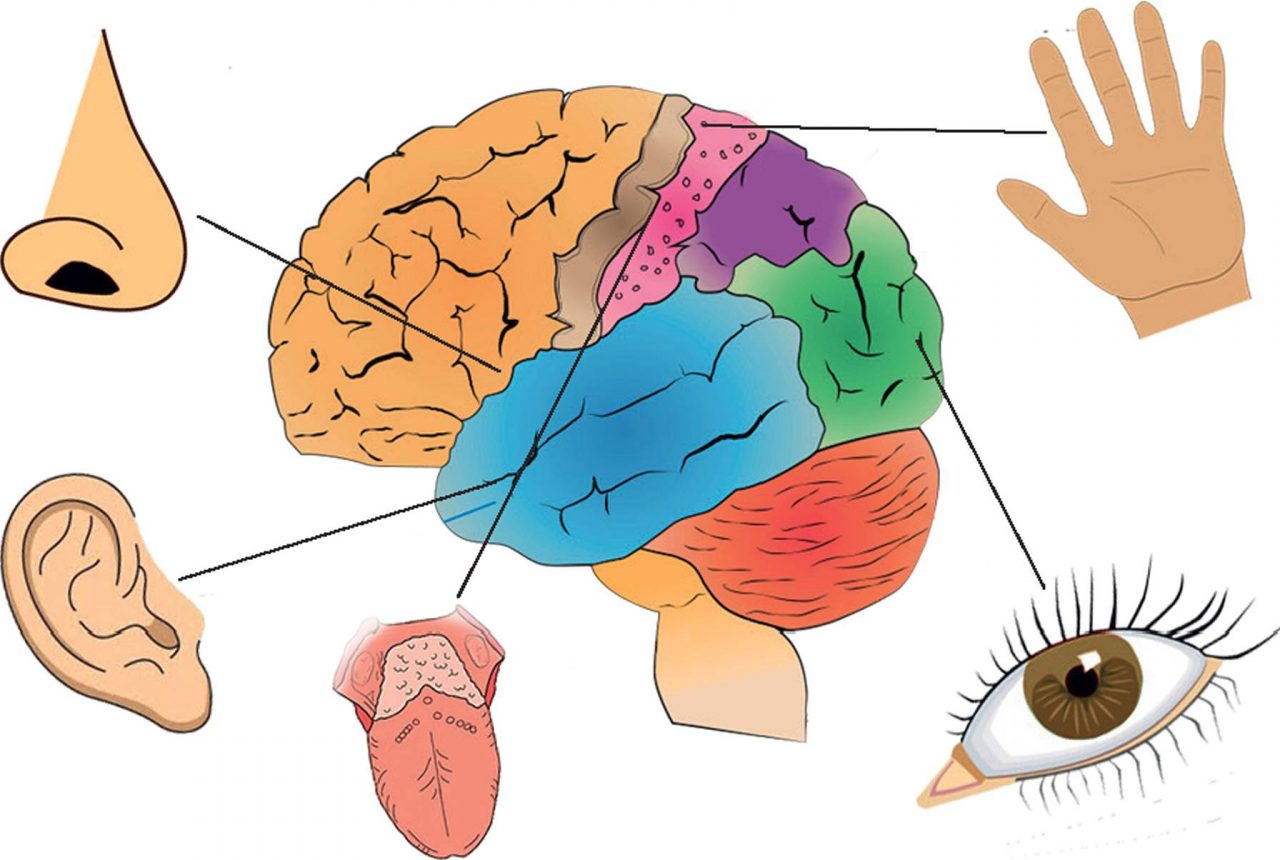

Изображения и визуализация внутренних органов человека